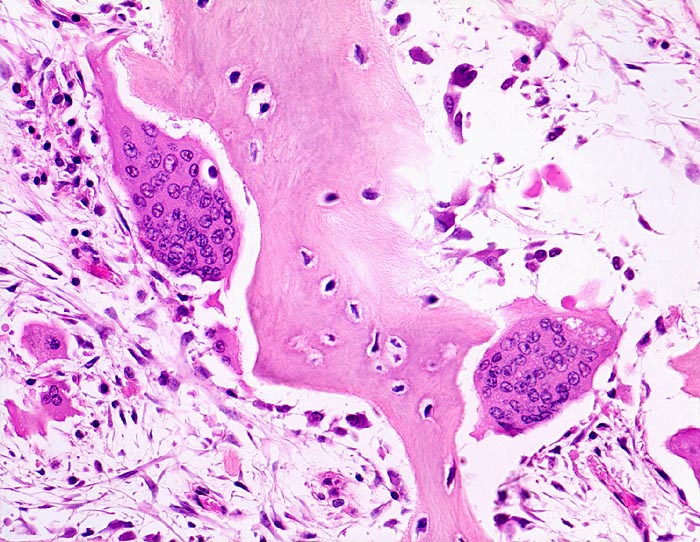

Pathologisch gesteigerter Knochenumbau: Riesenosteoklasten mit sehr zahlreichen Kernen bauen das Knochengewebe ab. Gleichzeitig finden sich auch vermehrte kubische aktive Osteoblasten, welche Knochen anbauen. Das Mark zeigt eine lockere Fibrose.

Die Patientin hatte wiederholt über Knieschmerzen geklagt. Autoptisch zeigte das Kniegelenk eine leichte Arthrose. Aus der auffallend verdickten Tibia wurde eine Gewebsprobe zur Untersuchung entnommen.